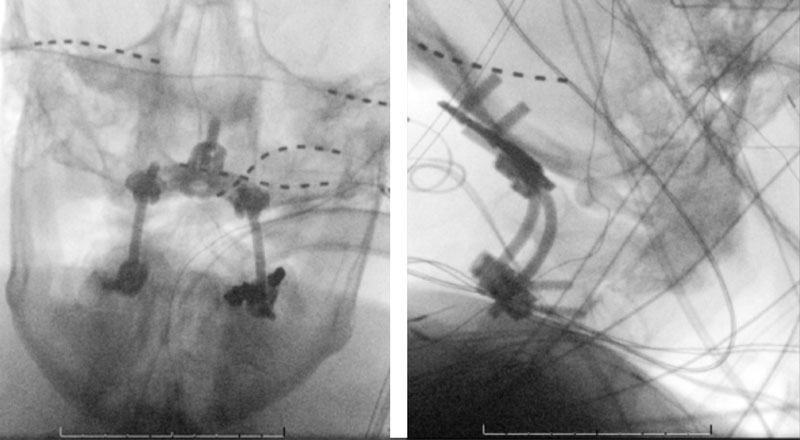

Dynamic provocative fluoroscopy failed to reveal significant Vertebral osseous instability (Figure 2A), however, Transcranial Doppler Flow velocities in the distal right Vertebral and Basilar Artery are markedly reduced during Extension of the Neck (Figure 2B).